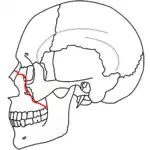

At the beginning of the 20th century, René Le Fort mapped typical locations for facial fractures; these are now known as Le Fort I, II, and III fractures (right).[7] Le Fort I fractures, also called Guérin or horizontal maxillary fractures,[14] involve the maxilla, separating it from the palate.[15] Le Fort II fractures, also called pyramidal fractures of the maxilla,[16] cross the nasal bones and the orbital rim.[15] Le Fort III fractures, also called craniofacial disjunction and transverse facial fractures,[17] cross the front of the maxilla and involve the lacrimal bone, the lamina papyracea, and the orbital floor, and often involve the ethmoid bone,[15] are the most serious.[18] Le Fort fractures, which account for 10–20% of facial fractures, are often associated with other serious injuries.[15] Le Fort made his classifications based on work with cadaver skulls, and the classification system has been criticized as imprecise and simplistic since most midface fractures involve a combination of Le Fort fractures.[15] Although most facial fractures do not follow the patterns described by Le Fort precisely, the system is still used to categorize injuries.[5]

| Le Fort III fractures | |